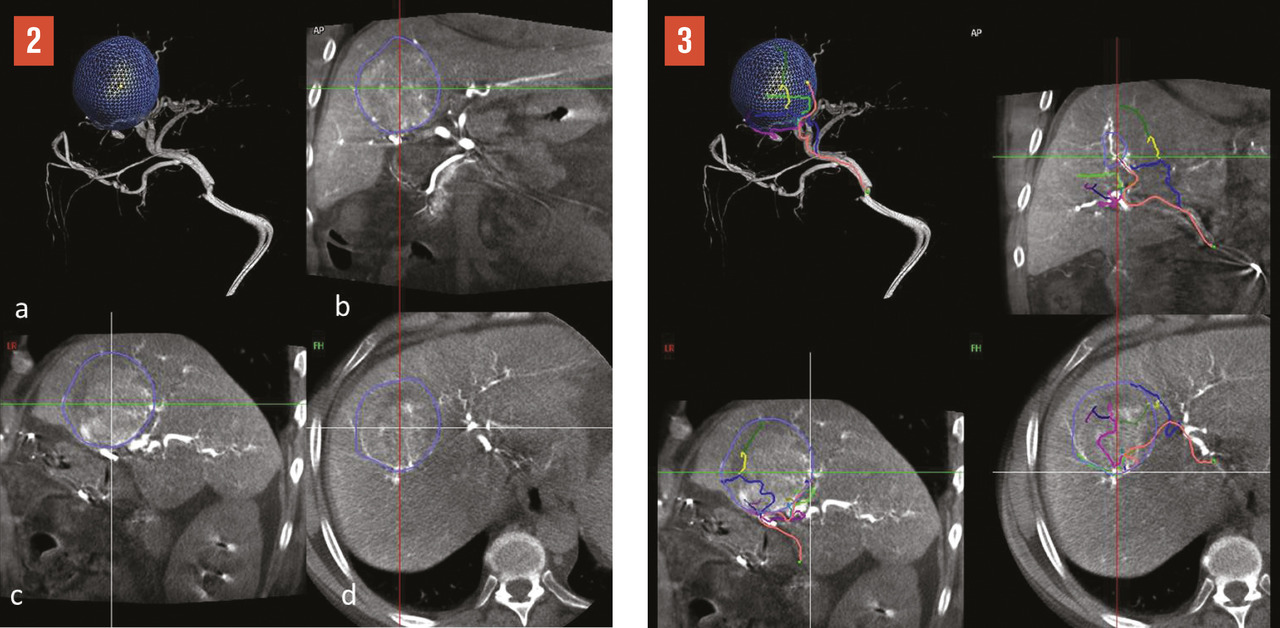

La radiologie interventionnelle a commencé à se développer grâce au progrès de la navigation intra- artérielle à l’aide de cathéters de plus en plus miniaturisés.3 Le positionnement de l’extrémité du cathéter dans l’artère hépatique, voire dans une de ses branches segmentaires à partir d’une voie d’abord périphérique le plus souvent fémorale, permet une obstruction (embolisation)4 [fig. 1 à 4 ], une libération locale intra-artérielle de chimiothérapie5 et plus récemment de microsphères chargées de médicaments6 ou de particules radioactives permettant une irradiation interne sélective du foie.7, 8 Le but est d’obtenir une concentration élevée des agents cytotoxiques au plus près des tumeurs dans le foie avec un faible relargage dans la circulation générale. Enfin, il est possible de placer par radiologie interventionnelle un cathéther dans l’artère hépatique relié à une cham-bre implantable (fig. 5 ). La chimiothérapie est ainsi injectée directement dans le système artériel du foie de façon répétée (en général toutes les deux semaines) avec des concen- trations intrahépatiques de médi- caments bien supérieures à celles obtenues après une injection par voie veineuse. L’objectif est d’obtenir une réduction tumorale qui permette au patient d’être éligible à une éventuelle chirurgie curative.9

Méthodes locorégionales par cathétérisme artériel

Il s’agit de l’injection locale dans le foie de médicaments, d’agent d’embolisation ou d’agents radioactifs. Après cathétérisme artériel à partir le plus souvent de l’artère fémorale et repérage des lésions, le radiologue interventionnel injecte localement différents types d’agents selon le type de métastases, l’extension de la maladie et les traitements antérieurs, après décision en réunion de concertation multidisciplinaire (fig. 1 à 4 ).